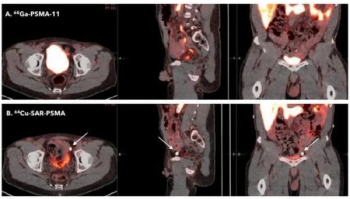

Currently in phase III trials, the 64Cu-SAR-bisPSMA PET agent reportedly offers a longer half-life and higher tumor uptake than other radiopharmaceuticals for prostate cancer imaging.